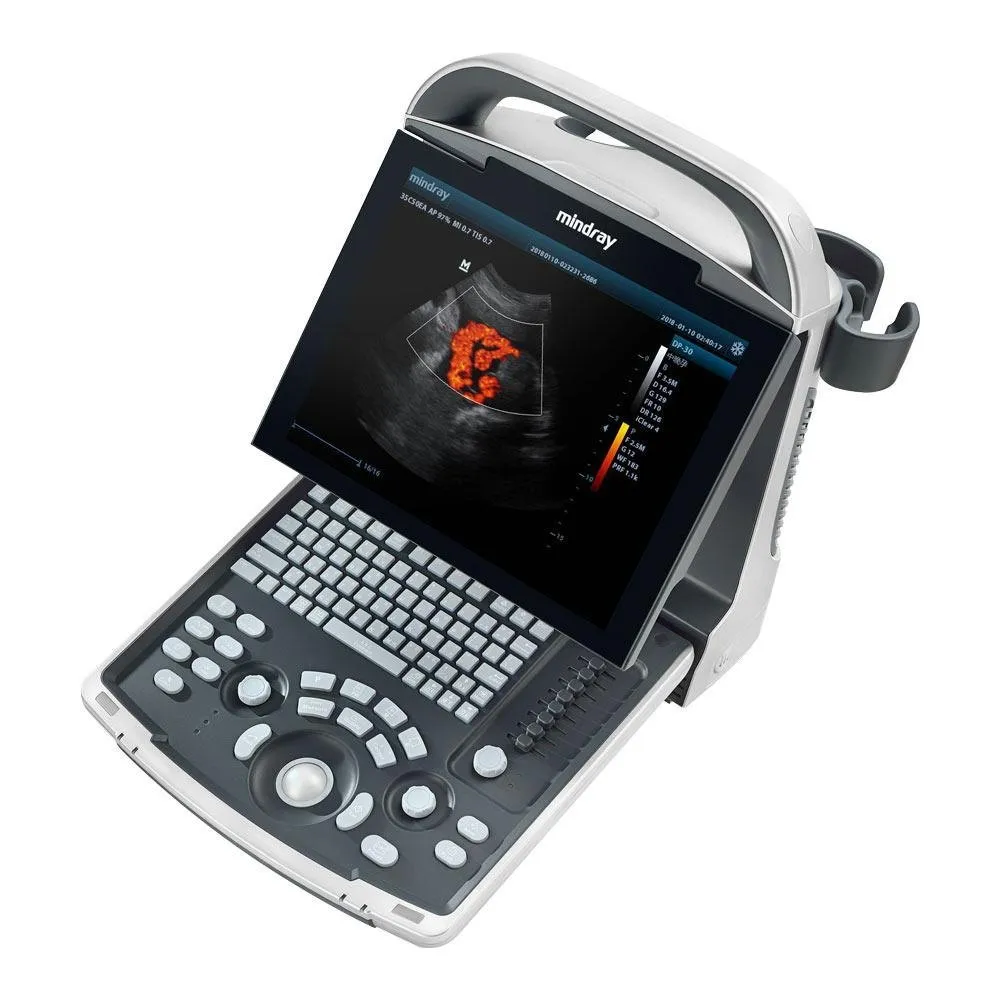

Mindray DP-21 Power Digital Ultrasound Machine

Mindray DP-21 Power Digital Ultrasound Machine

An ideal choice for an entry-level black & white ultrasound system, DP-20 comes equipped with a best-in-class combination of performance and affordability. With a new platform based on Intel’s powerful processor, DP-20 forms an integral part of Mindray’s new generation of portable B/W ultrasound systems equipped with the latest imaging technologies and convenient workflow options.

- iClear for Speckle Reduction Imaging, providing clear and sharp lesion contours.

- Sharper & Continuous Edges

- Smooth Uniform Tissues

- Cleaner ‘no echo areas